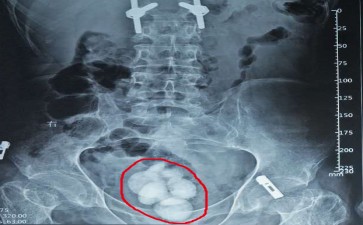

你有没有想过,身体里的小石头——长春结石医院膀胱结石,可能是生活方式的“警报器”?它不像感冒那样突然来袭,却可能在不经意间,用排尿时的刺痛、尿频尿急,甚至血尿,提醒你:该关注健康了!

长春结石医院膀胱结石的形成,往往与三个“幕后黑手”有关。一是尿路梗阻,比如前列腺增生、尿道狭窄,让尿液像堵车的河流,在膀胱里滞留,矿物质趁机沉淀成石。二是感染,某些细菌能分解尿素,让尿液变碱,磷酸盐、碳酸盐就像被施了魔法,纷纷结晶成石。三是代谢异常,甲状旁腺功能亢进、痛风等疾病,会让尿液中钙、尿酸等成分超标,结石自然找上门。

别小看这些“小石头”,它们可是“麻烦制造机”。排尿时像刀割一样疼,尿流突然中断,甚至尿潴留,都可能是结石在捣乱。更可怕的是,长期刺激膀胱黏膜,还可能诱发膀胱癌。

不过,长春结石医院膀胱结石并非不可战胜。多喝水,让尿液像清泉一样冲刷膀胱,减少结石形成的机会;少吃高草酸、高嘌呤食物,避免给结石“添砖加瓦”;及时治疗前列腺增生、尿道狭窄等疾病,解除尿路梗阻的“封锁线”。如果结石已经形成,也别慌,小结石可通过药物、运动促进排出,大结石则有膀胱镜取石、体外冲击波碎石等“高科技武器”帮忙。